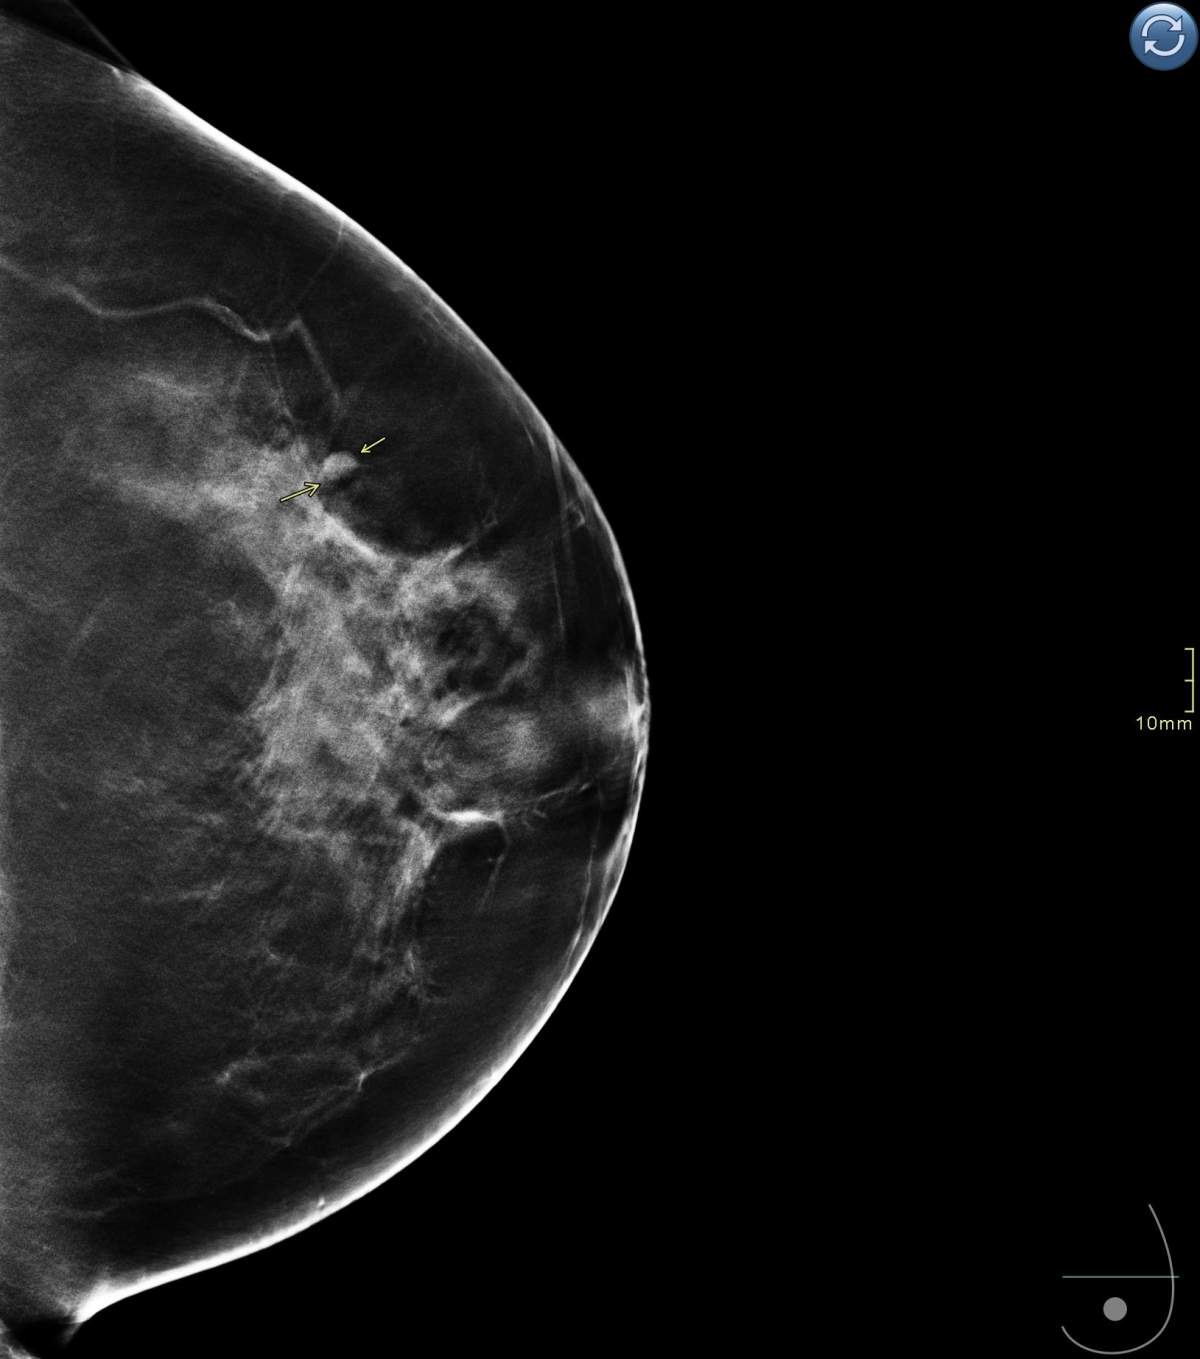

The imaging is called digital breast tomosynthesis and is a type of 3D imaging. Researchers out of Lawson Research Institute want to learn whether it is better at finding abnormalities than the conventional digital 2D mammogram.

During a tomosynthesis exam, the x-ray tube moves in an arc over the compressed breast and captures multiple images from different angles.

This is different from a conventional 2D mammogram, in which two X-ray images are taken of the breast: one from top to bottom, the other from side to side at an angle.

After the images are taken in the 3D exam, they are reconstructed into a set of 3D images by a computer which allows radiologists to examine the breast at multiple layers of depth, making it easier to distinguish normal breast tissue from potential abnormalities.

“By adding the three-dimensional views, we can separate the tissue and add to the [clarity] of our breast cancer efforts, which will hopefully lead to detecting breast cancer at an earlier stage,” said Kornecki.